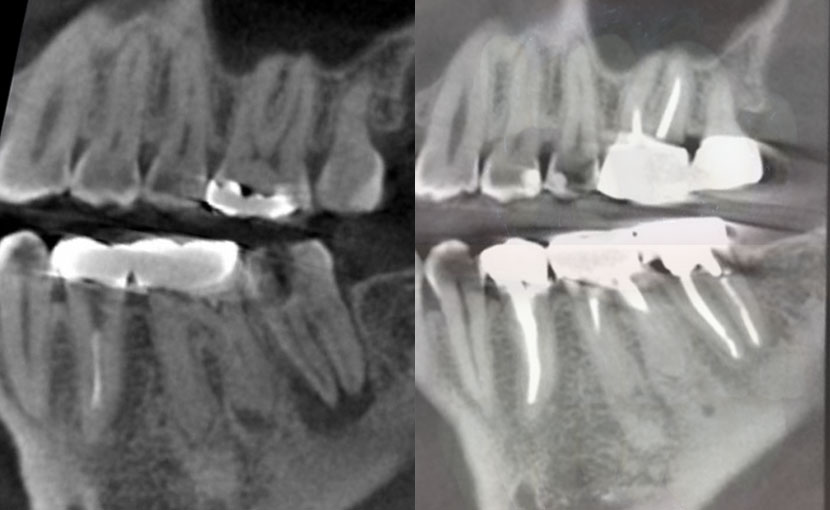

術直後CT画像

きちんと化膿部分がソウハされ、三次元的にも根っこの先にMTAと呼ばれる薬が緊密に充填(逆根充)されているのが認められます。

術後10年後CT画像前頭断

抜歯適応と考えられた歯が、10年以上経過しても、患者さんが不都合を訴えることなく、問題なく機能しています。その証拠として、歯科用部分CTを撮影してみると、三次元的に根っこの先の黒い骨透過像は消失し、骨が添加していることが認められます。